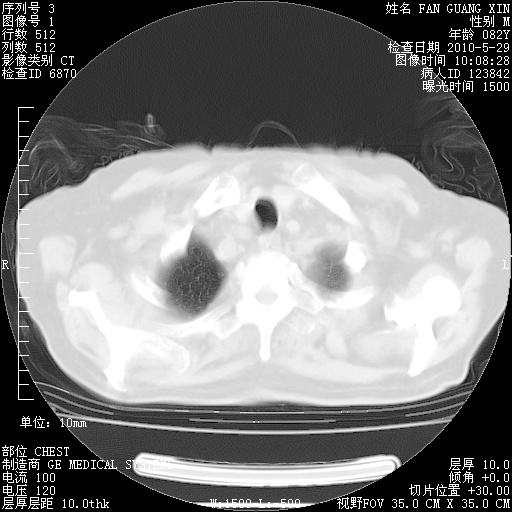

再治疗10天后的肺部CT

再治疗10天后的肺部CT 纵膈窗